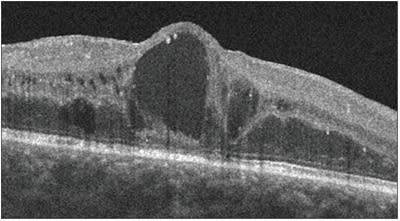

OCT demonstrates basic structural changes from DME.

OCT demonstrates the three basic structural changes of the retina from DME: retinal edema, retinal cysts and serous retinal detachment. OCT is not currently required to establish a macular edema diagnosis and is not compelled by practice guidelines; however, OCT has gained popular acceptance as an additional technique to help identify and evaluate macular pathology.3 Quantitative measurement of macular thickness and analysis of the foveal architecture allow for a precise and reproducible way to monitor macular edema.